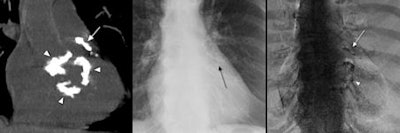

| Left, CT coronal reconstruction of calcium in the left anterior descending (LAD) artery (white arrow), aortic valve (white arrowhead), mitral valve (white arrowhead), and descending aorta (white arrowhead). Center, corresponding standard posteroanterior radiograph suspicious of CAC (black arrow). Right, corresponding DE image demonstrating calcium in the LAD within the CAC triangle (white arrow) and mitral annulus (white arrowhead). The aortic valve is not well visualized as it is impeded by the spine. Future studies on DE should focus on testing left anterior oblique projections for improved visualization of the right coronary artery and the aortic valve. Images courtesy of Dr. John Mafi. |

To assess the efficacy of the technique, the researchers compared the DE scores to the CT-based CAC scores, and found that DE correlated with CT 87% of the time (p < 0.0001).

Mafi said the technique showed strong positive predictive value (PPV), particularly in patients with CT-based CAC scores greater than 400, with a PPV of 100% at this level. It did less well in patients with CAC scores less than 400, scoring a negative predictive value of 52%, indicating that these patients might require follow-up CT.

In future research, Mafi and colleagues hope to improve upon the DE technique by using electrocardiographic gating to reduce motion artifacts. In addition, left anterior oblique image acquisitions could be used rather than the standard posteroanterior view, in which the right coronary artery is sometimes blocked by the spine.